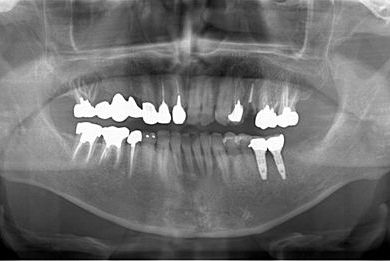

| 性別/年齢 | 男性 / 53歳 | ||||||||||||||||||||||||||||||||

| 主訴 | 左下奥歯2本のインプラント治療を希望。 | ||||||||||||||||||||||||||||||||

| 治療方針 | 左下欠損部分をインプラント治療にて機能的・審美的回復を行う。 | ||||||||||||||||||||||||||||||||

| 治療内容 | インプラント2本、ハイブリッドセラミッククラウン2本 | ||||||||||||||||||||||||||||||||

| 総治療費 | 399,000円 | ||||||||||||||||||||||||||||||||

| 治療期間 | 9ヶ月 |